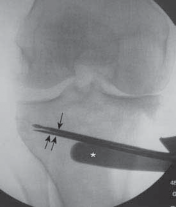

TECH FIG 4•A.

Fluoroscopic image showing the thin osteotomes completing the osteotomy cut to within 1 cm of the lateral cortex.

Single black arrow,

osteotomy guide pins;

double black arrows

, osteotome;

, posterior retractor protecting the neurovascular structures.

B.

Stacking the osteotomes in the osteotomy cut to help provide the initial plastic deformation of the lateral cortex.

C.

An osteotomy wedge impacted into the osteotomy cut. The anterior tine reads 10 mm and the posterior tine reads 11 mm, because the proximal tibia is a triangle, as explained in Figure 1A. The laser lines correspond with the desired osteotomy opening angle.

D.

Another view of the osteotomy wedge inserted into the osteotomy site.

E.

Fluoroscopic image showing the osteotomy wedge in place with the guide pins just superior to it. The guide pins are left in place during the opening of the osteotomy to avoid inadvertently propagating the osteotomy. The alignment rod is relied upon to verify the amount of opening of the osteotomy and the change in the mechanical axis.

, osteotomy wedge;

black arrow,

guide pins;

arrowhead,

alignment rod.

F.

The osteotomy wedge handle has been removed, and the posterior tine is seen almost at the level of the posteromedial cortex to avoid the inadvertent increase in tibial slope.